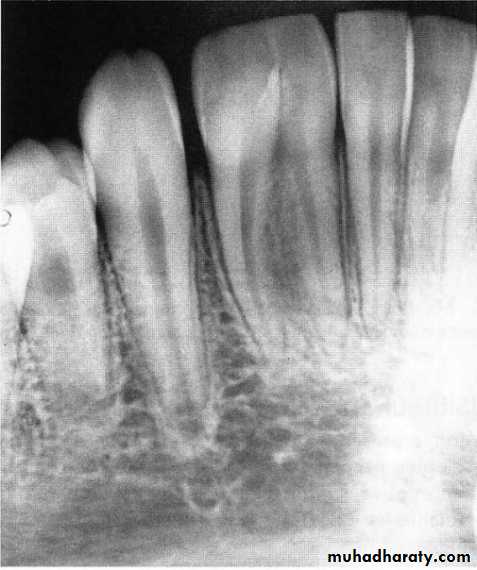

Pulp pathosis of the primary molars in the form of lamina dura breakdown occurs in the furcation areas while in the permanent teeth occurs at the apical area(apex).

The radiograph may show that the fusion is limited to the crowns and roots. Fused teeth will have separate pulp chambers and separate pulp canals